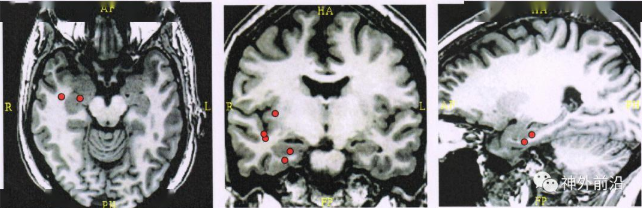

图1磁共振 MRI扫描未发现特殊异常

多学科会诊:患者有明确先兆,恐惧,似曾相识,发作表现为愣神,自动症,为较典型的复杂部分性发作,结合脑电图、脑磁图右颞放电,神经心理评估颞叶功能损伤为主,PET-MRI融合图像显示右颞极海马轻度代谢减低,考虑颞叶癫痫,右颞致痫起源可能性大。但患者MRI阴性,所以建议进一步行颅内电极置入***定位癫痫起始区。

手术方案:“ROSA ONE”引导下右侧颞叶、岛叶等部位置入深部电极8根。